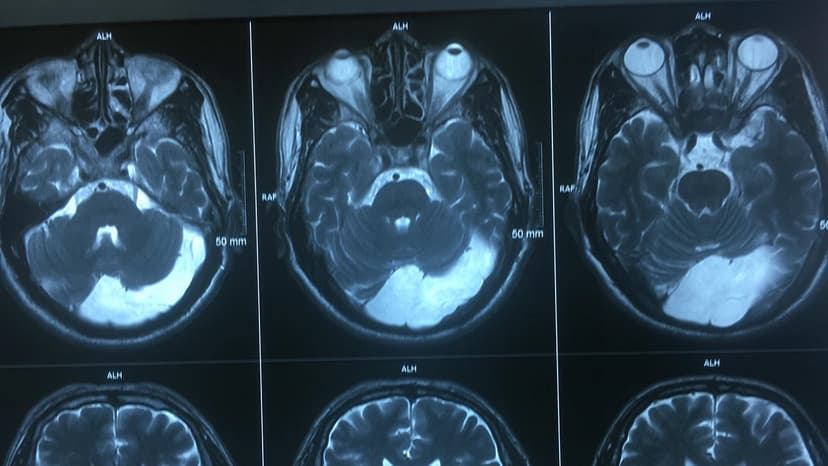

Hình ảnh chụp X-quang sọ não